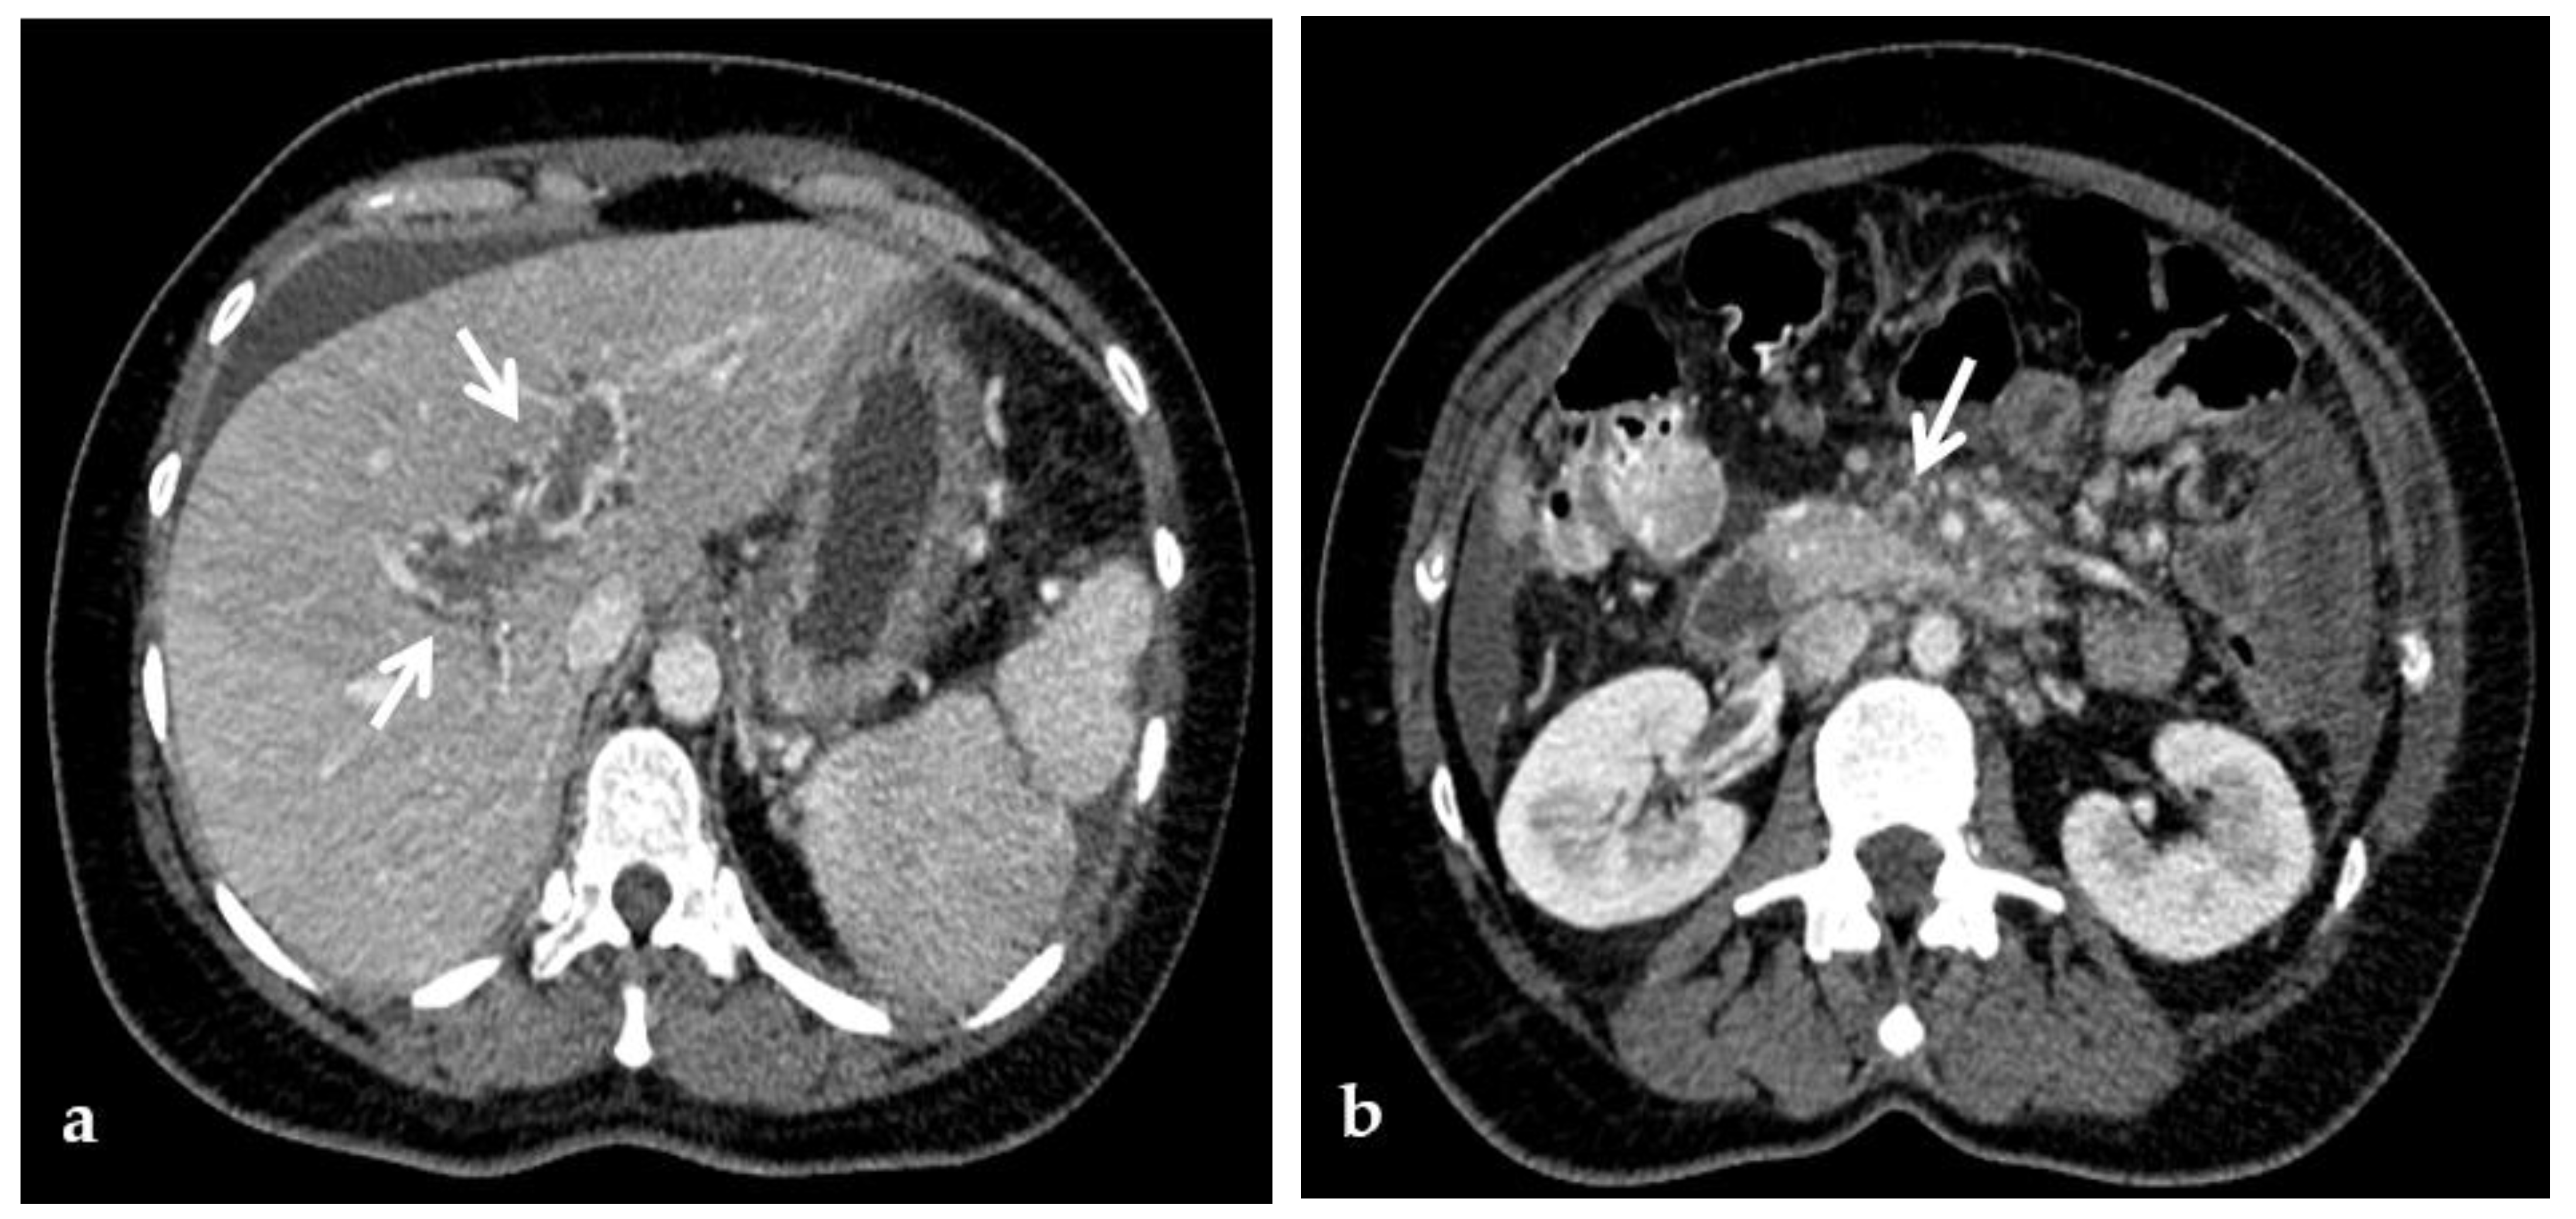

Figure 11.

Anteroposterior view of a percutaneous transmesenteric portography imaging series of an acute complete portal vein thrombosis occurred early after pediatric split-liver transplantation in a 1-year-old female with biliary atresia. (a) Superior mesenteric portography performed through a surgically-placed transmesenteric sheath (white arrow) shows total occlusion of the main portal vein and its intrahepatic branches, with opacification of several portosystemic varices (black arrows). (b) Superior mesenteric portography shows effective embolization of the portosystemic shunts to reduce the flow-steal phenomenon. A mixture of N-butyl cyanoacrylate and iodized oil and metallic microcoils (arrows) were used. (c) Portography image shows angioplasty with a 5-mm non-compliant balloon catheter performed on a stiff guidewire advanced through the common portal vein (white arrow). Note the spontaneous remaining opacification caused by the mixture of N-butyl cyanoacrylate and iodized oil (black arrows). (d) Final superior mesenteric portography shows restored opacification of the portal vein anastomosis, the umbilical recess of the portal vein (black arrow) and the intrahepatic segment 2 and segment 3 branches (white arrows), with no contrast filling of the portosystemic shunts.